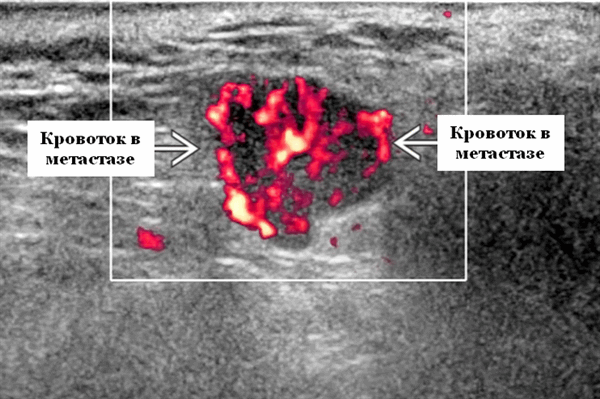

Цветной допплер. Узловая НХЛ. Выраженная центральная или внутриузловая гиперваскуляризация. Паренхима при неходжкинской лимфоме более диффузная железистая гиперваскуляризация. Васкуляризация от умеренной до выраженной в плохо очерченных образованиях.

- Узловая неходжкинская лимфома (НХЛ): одиночные или множественные увеличенные яйцевидные внутрипаротидные лимфатические узлы, которые на УЗИ гомогенно гипоэхогенны по отношению к паренхиме околоушной железы, эхо-картина сетчатая. Заднее акустическое усиление. Выраженная внутриузловая гиперваскуляризация